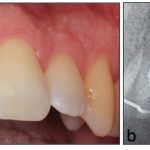

Fallstricke in der Endodontologie

NewsZahnmedizin

Die endodontische Therapie stellt hohe Anforderungen an Diagnostik, Planung und technische Umsetzung, bietet jedoch bei leitliniengerechtem Vorgehen eine prognostisch günstige und substanzschonende Möglichkeit zum Zahnerhalt.…